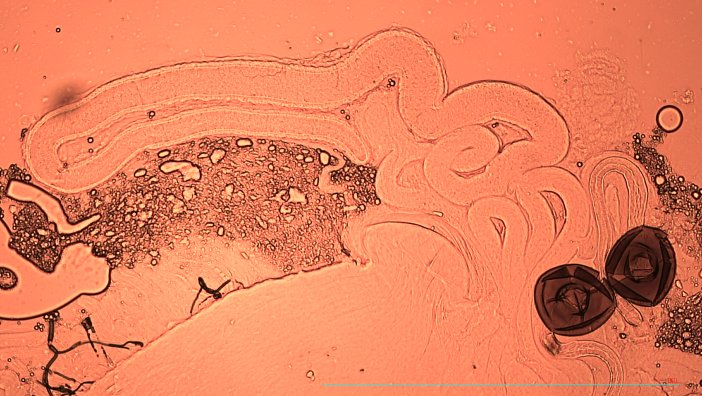

Kapak görseli: Bir dişi Drosophila meyve sineğinin sperm keselerindeki (özelleşmiş uzun süreli sperm depolama organı) yeşil floresan protein ile işaretlenmiş spermler. Görsel: Krish Sanghvi